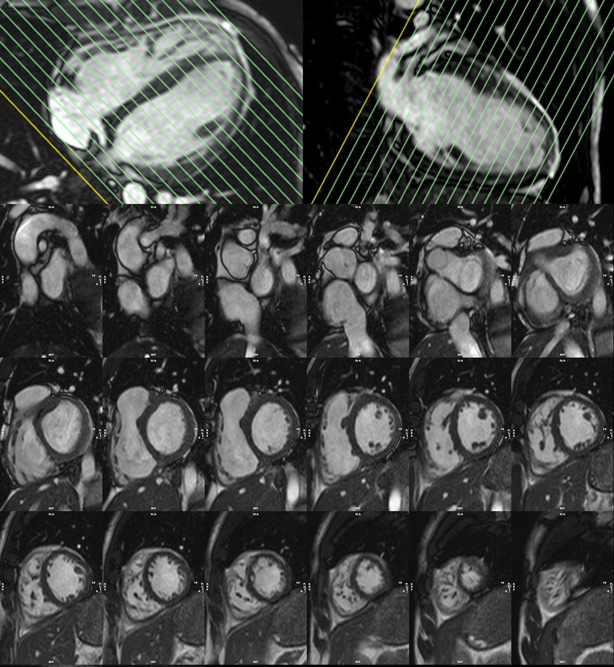

3. bSSFP左室短軸像シネMRI(Fig. 3

4. bSSFP長軸像シネMRI(Fig. 5

Pediatric Cardiology and Cardiac Surgery 40(4): 260-271 (2024)

Fig. 3 Top: Planning of the short axis image plane parallel to the mitral valve in the 4 chamber long axis plane (left) and 2 chamber long-axis plane (right). Bottom: 18 short axis cine slices shown from base (top left) to apex (bottom right).

Fig. 4 Left: White blood axial scout image through the base of the left ventricle (LV) and right ventricle (RV). Planning of the 2 chamber long axis is shown by the white line. Center: White blood 2 chamber long axis scout image. Planning of the 4 chamber long-axis is shown by the white line. Right: White blood 4-chamber long axis scout image.

Fig. 5 Left: 4-chamber long axis cine image. Center: 2-chamber long axis cine image. Right: 3-chamber long axis cine image.